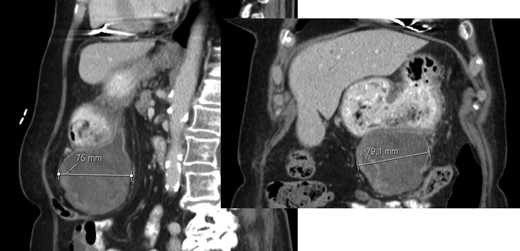

A 26-year-old woman, with past medical history of removal of hemangiopericytoma of the right leg, was referred to our Hepatobiliary Unit due to a liver tumor that was discovered on abdominal-pelvic computed tomography (CT) scan, performed after complaints of epigastric pain. CT scan (Fig. 1) showed a voluminous, heterogeneous, hypervascular mass, occupying segments 4, 5 and 8, with 19 cm in diameter, as well as suspicious lesion on left iliac bone suggestive of solitary fibrous tumor metastasis.

Abdomino-pelvic computed tomography (AP-CT) – voluminous heterogeneous liver mass in segments 4, 5 and 8 with 19 cm in diameter.